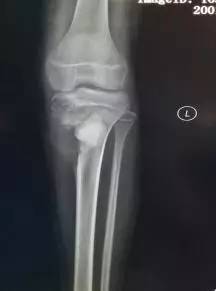

【病例】胫骨骨肉瘤1例X线影像表现

患者,女,12岁,左小腿进行性疼痛2月余,加重1月。

X线主要表现有成骨性的骨硬化灶或溶骨性的破坏,骨膜反应可见Codman三角或呈“日光照射”现像。CT检查可以确定髓内及软组织病变范围,对定性帮助不大。磁共振成像诊断价值与CT基本相同。肿瘤在髓内及软组织范围显像较CT清楚。

1.X线表现:主要表现有成骨性的骨硬化灶或溶骨性的破坏,骨膜反应可见Codman三角或呈“日光照射”现像。